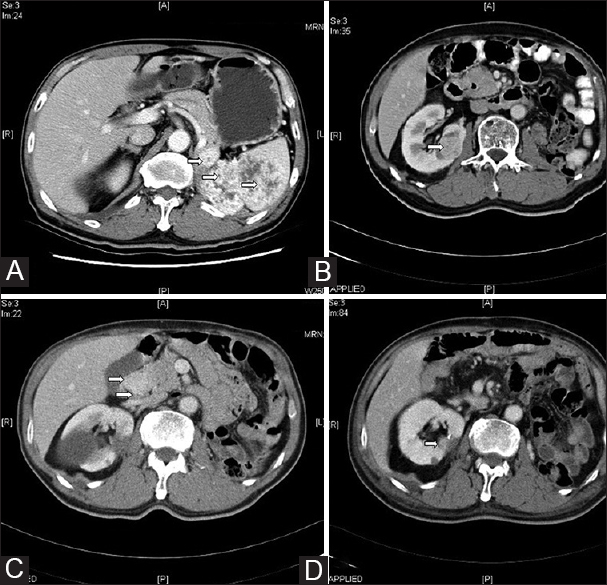

Metastasis of renal cell carcinoma to the pancreas is uncommon and, in most cases, presents as a single pancreatic mass that shows a more favorable prognosis than primary pancreatic tumors. We examined patients with renal cell carcinoma metastatic to the pancreas, and discuss the clinical findings, treatment administered, and final outcomes. The present study is a retrospective analysis of renal cell carcinoma patients with pancreatic metastasis. Pancreatic tumor specimens were obtained by surgical excision, surgical biopsy, fine-needle biopsy, or endoscopic ultrasound biopsy. The surgical approaches included distal splenopancreatectomy, total pancreatectomy, or distal pancreatectomy. The physician determined the postoperative treatment regimen with interferon-α or targeted therapy on the basis of patient's performance. A total of six patients with median age of 50 years were included in the study. The median time from the primary nephrectomy to the development of pancreatic metastasis was 16 years. In the biopsy-only group, the mean stable disease period was 16.5 months. In the patients treated with surgery combined with interferon-α or targeted therapy, the mean stable disease period was 29.5 months. The patients treated with repeat mastectomy showed a mean stable disease period of 33.3 months. Aggressive surgical management is more effective than observation or immunotherapy. Recent advances in the design of targeted therapies may provide alternative treatment strategies. Combination therapy may play an important role in the future. Considering patient compliance and cost-effectiveness, resection of pancreatic metastasis is currently the first choice of treatment.